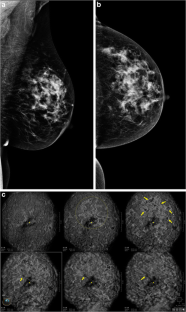

Fig. 4